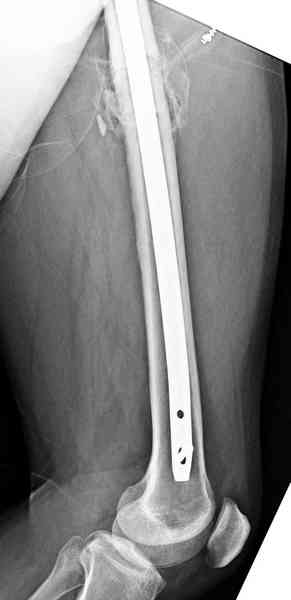

и проведены шурурпы через и спереди штифта без удаления.

Послеоперационные снимки